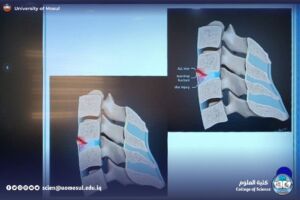

MRI: تبسيط مبدأ T1 وT2، وفهم التباين العالي للأنسجة، وأهم استخداماته في الدماغ والعمود الفقري.